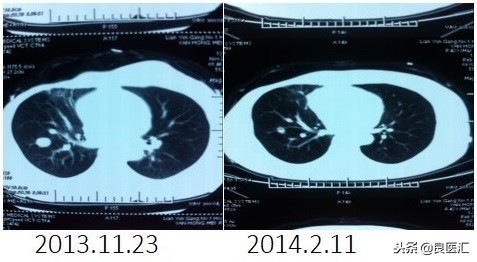

2013-11-23全面复查发现肺转移。 DFS=35个月

患者自2013-11-26起给予曲妥珠单抗(440mg d1)/脂质体紫杉醇(240mg d2)/CBP(500mg d2)方案化疗一个周期,出现Ⅱ度骨髓抑制,因患者主诉乏力明显,后修改方案曲妥珠单抗(330mg 每 3周重复)/脂质体紫杉醇(120mg d1+d8+d15,每4周重复)化疗,化疗过程顺利,患者无明显骨髓抑制,无乏力主诉,于2014-02-11全面复查,疗效评价为PR。